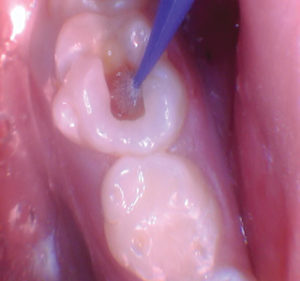

Figura 2. La exposición pulpar se produjo al excavar la dentina infectada (la exposición pulpar no se capturó en la foto). |

Figura 4. Después de excavar el tejido pulpar en los orificios del canal, se utilizó una prenda de algodón seco para evaluar la salud de la pulpa mediante la aplicación de hemostasia por presión. |